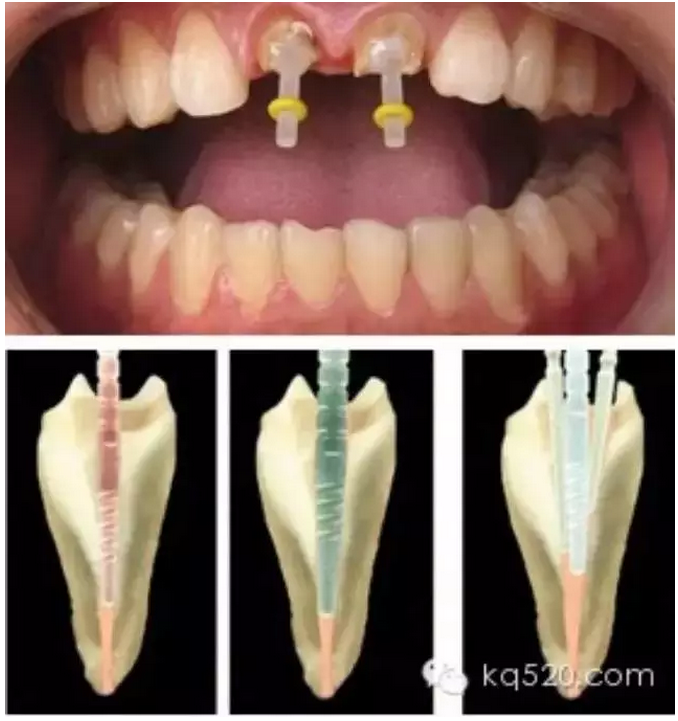

牙齒的外層組織是非常堅硬耐磨的,但是其內(nèi)部卻是一個空腔,里面分布著許多血管和神經(jīng),我們將內(nèi)部這些柔弱的組織稱為“牙髓”。當牙髓發(fā)生炎癥的時候,就會引發(fā)疼痛,稱之為“牙髓炎”。在過去,對于這種牙髓炎采用的治療方法是:將牙齒鉆開,使用藥物將牙齒內(nèi)部發(fā)炎的牙髓“爛掉殺死”,從而緩解疼痛,這就是俗稱的“爛神經(jīng)”??梢?,“爛神經(jīng)”這種稱謂指代的是一些早期的治療手段。隨著治療觀念的全面革新和治療技術的巨大進步,這種治療方法已經(jīng)基本上被淘汰了?,F(xiàn)代普遍采用的是“根管治療”的方法。

前面我們講過,牙齒內(nèi)部實際上是一個空腔,這個空腔我們稱之為“根管系統(tǒng)”。同單純的“爛神經(jīng)”相比,“根管治療”不僅僅是要將“根管”中的牙髓“殺死”,還要將牙髓從“根管”中清除出來,然后要進行徹底清理和嚴格消毒,并用人工的充填材料將“根管”嚴密填塞。這就是所謂的“根管治療”。一個“根管治療”做得是否完善,會在很大程度上決定了這顆牙齒的壽命。而且,不僅僅是對于牙髓炎,牙齒的其他疾病(如根尖周炎等)也需要采用根管治療的方法才能得到治愈。從傳統(tǒng)的根管治療三部曲(即根管預備、根管消毒和根管充填)來講,一般的根管治療需要三次。但是這僅僅是理論上的情況,實際上因患者而異,因牙而異,因醫(yī)生的技術水平而異?,F(xiàn)代根管治療技術有了飛躍性的發(fā)展,有些根管治療甚至可以一次完成。